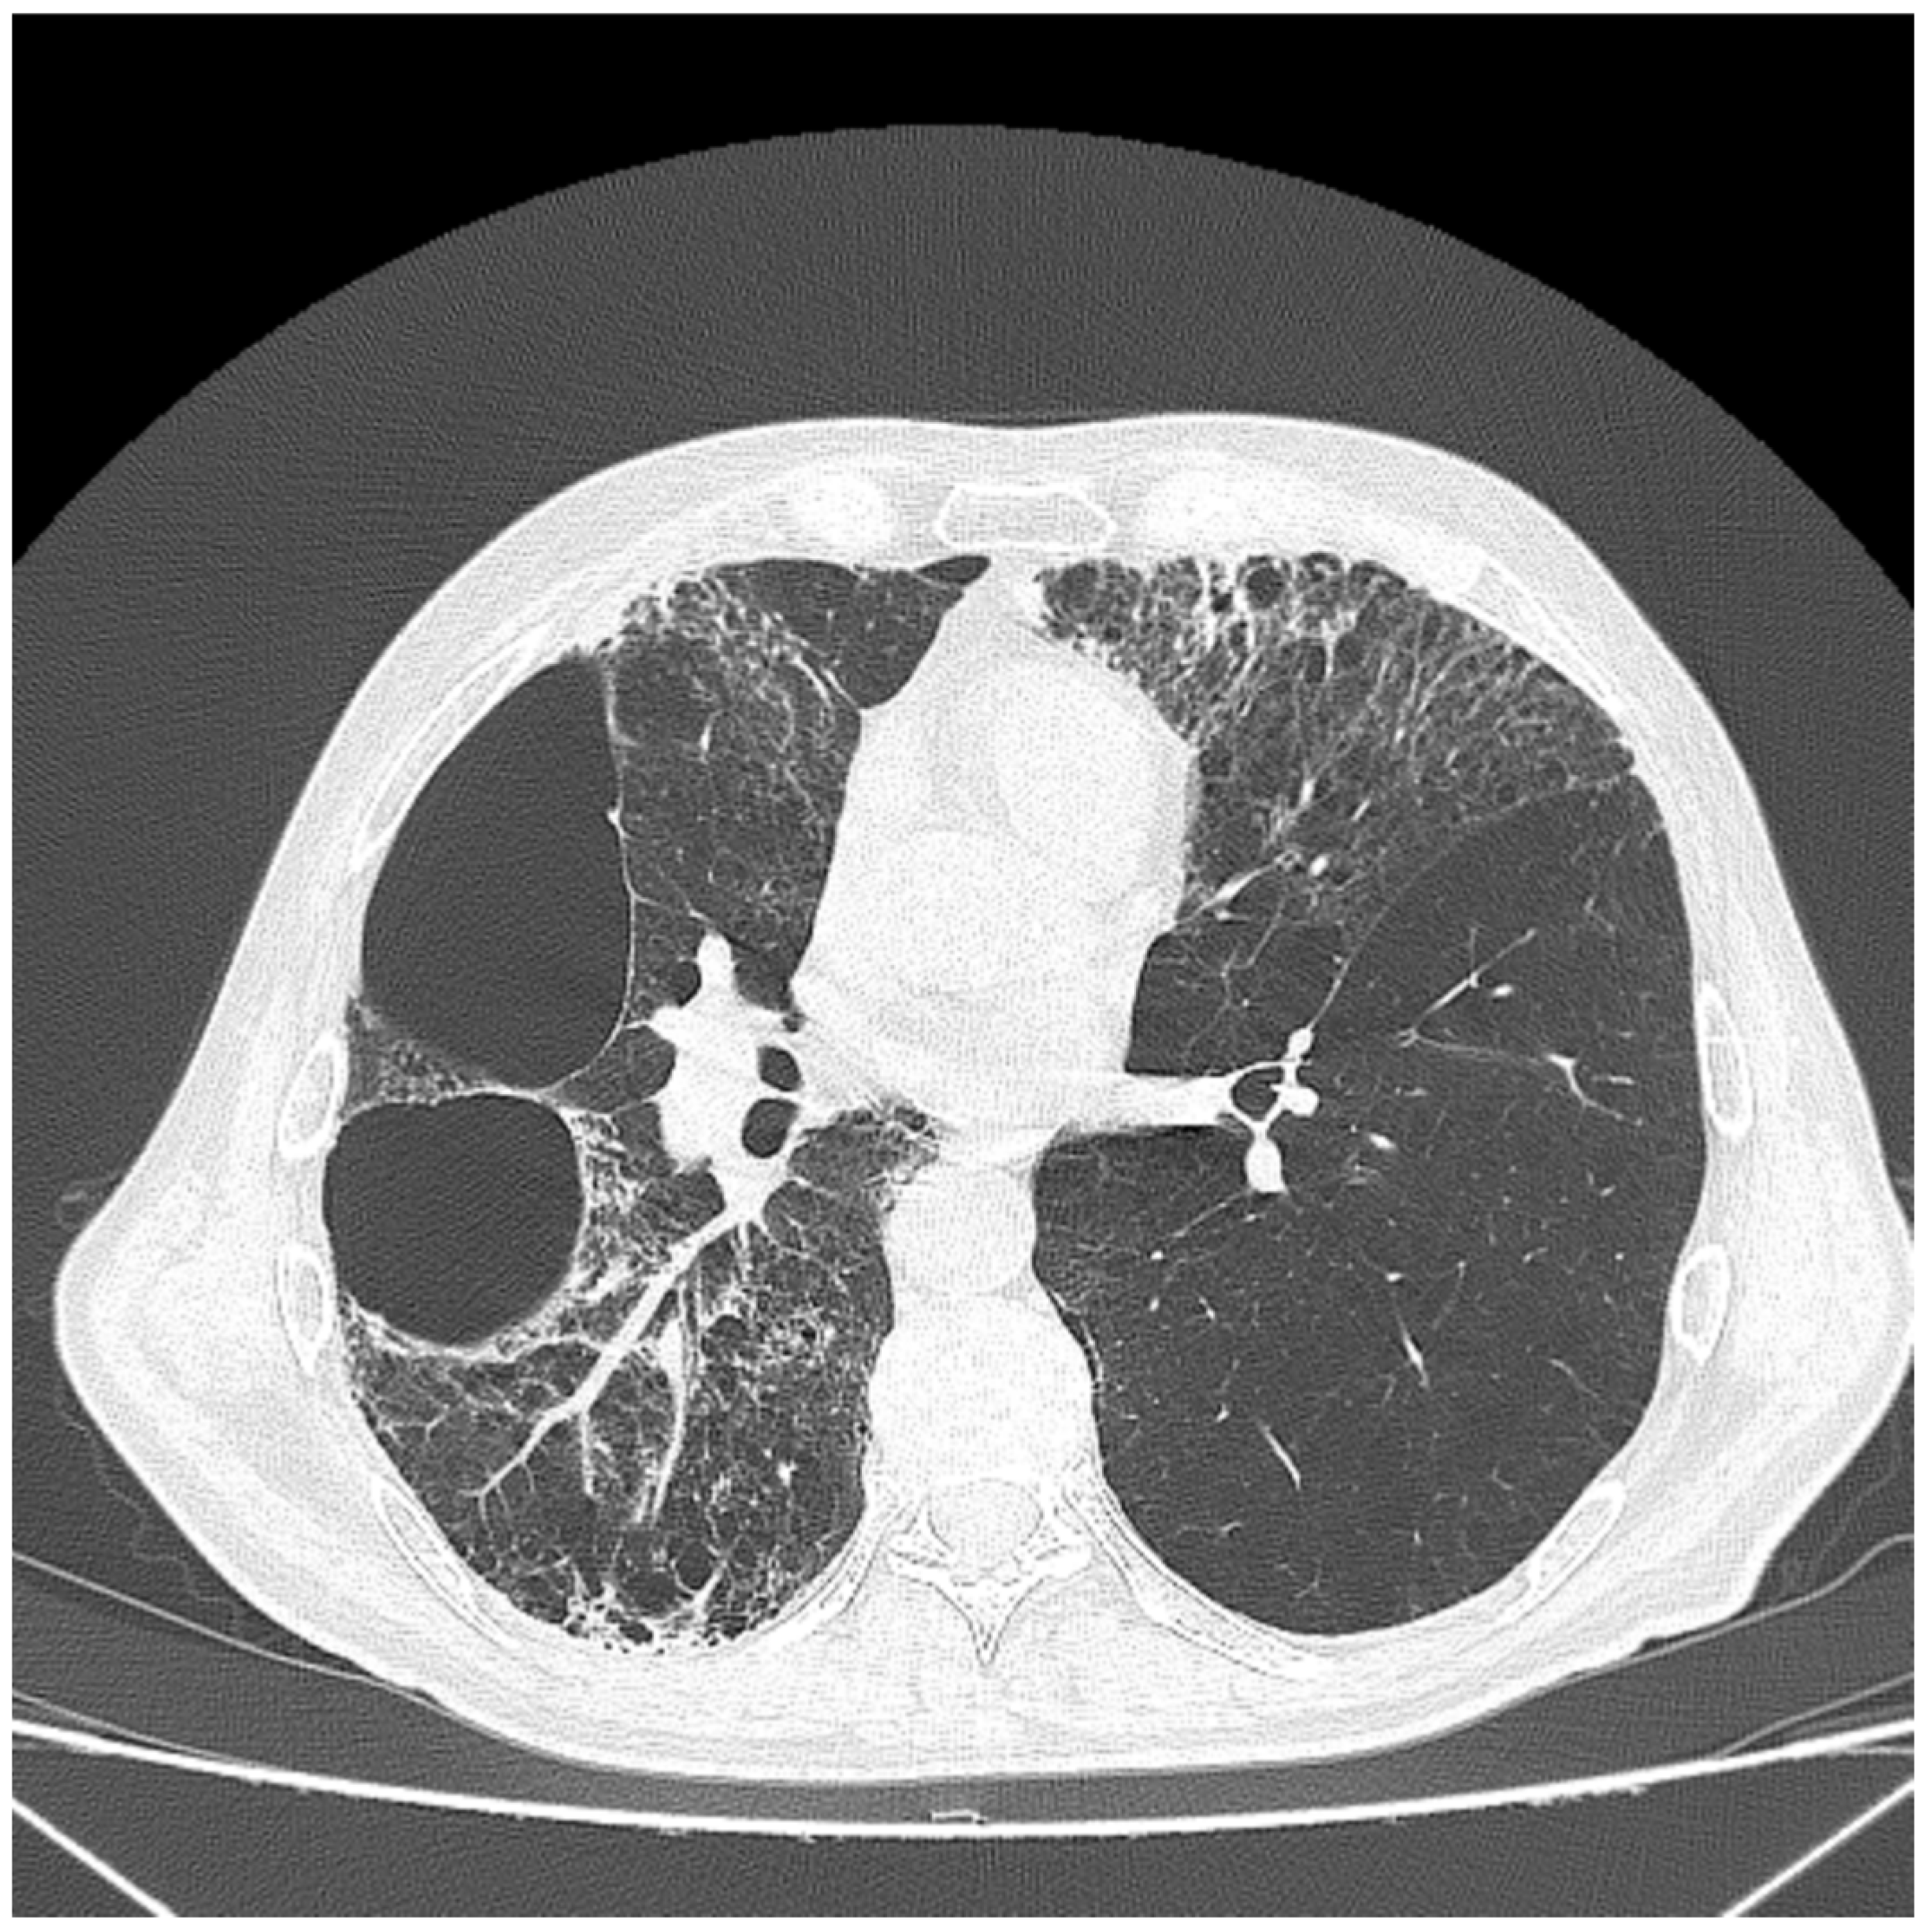

2. Case Report

3.2. Imaging Diagnosis